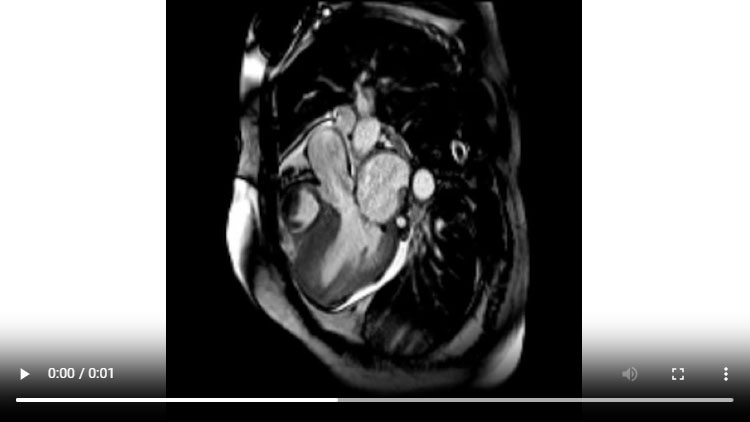

Figure 1A : Séquence Ciné-IRM - Coupes petit-axe basal

Figure 1B : Séquence Ciné-IRM - Coupes petit-axe médian

- Présence d’une hypertrophie ventriculaire gauche (HVG) asymétrique à prédominance septale mesurée au maximum à 23 mm.

- Visualisation de la sonde de PM avec artéfacts métalliques modérés au niveau du ventricule droit (flèches roses).

- Présence d’un épanchement péricardique de moyenne abondance (flèches rouges).